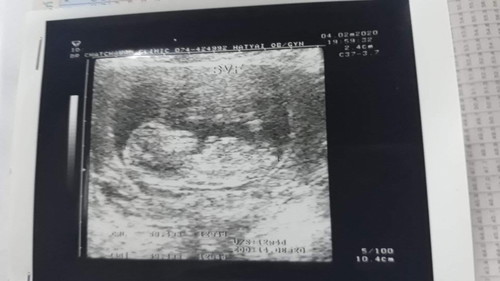

อัลตร้าซาวด์ครั้งแรก น้องดิ้นแรงมาก อยุ่ไม่นิ่งเลยลูก น้องมีแขนมีขาแล้วน๊า 13สัปดาห์ กำหนดคลอด10สิงหาค่ะ ขอดูท้องแม่ๆคลอดสิงหาหน่อยค่ะ